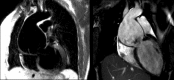

Elective root replacement in Marfan syndrome has improved life expectancy in affected patients. Three forms of surgery are now available: total root replacement (TRR) with a valved conduit, valve sparing root replacement (VSRR) and personalised external aortic root support (PEARS) with a macroporous mesh sleeve. TRR can be performed irrespective of aortic dimensions and a mechanical replacement valve is a secure and near certain means of correcting aortic valve regurgitation but has thromboembolic and bleeding risks. VSRR offers freedom from anticoagulation and attendant risks of bleeding but reoperation for aortic regurgitation runs at 1.3% per annum. A prospective multi-institutional study has found this to be an underestimate of the true rate of valve-related adverse events. PEARS conserves the aortic root anatomy and optimises the chance of maintaining valve function but average follow-up is under 5 years and so the long-term results are yet to be determined. Patients are on average in their 30s and so the cumulative lifetime need for reoperation, and of any valve-related complications, are consequently substantial. With lowering surgical risk of prophylactic root replacement, the threshold for intervention has reduced progressively over 30 years to 4.5 cm and so an increasing number of patients who are not destined to have a dissection are now having root replacement. In evaluation of these three forms of surgery, the number needed to treat to prevent dissection and the balance of net benefit and harm in future patients must be considered.